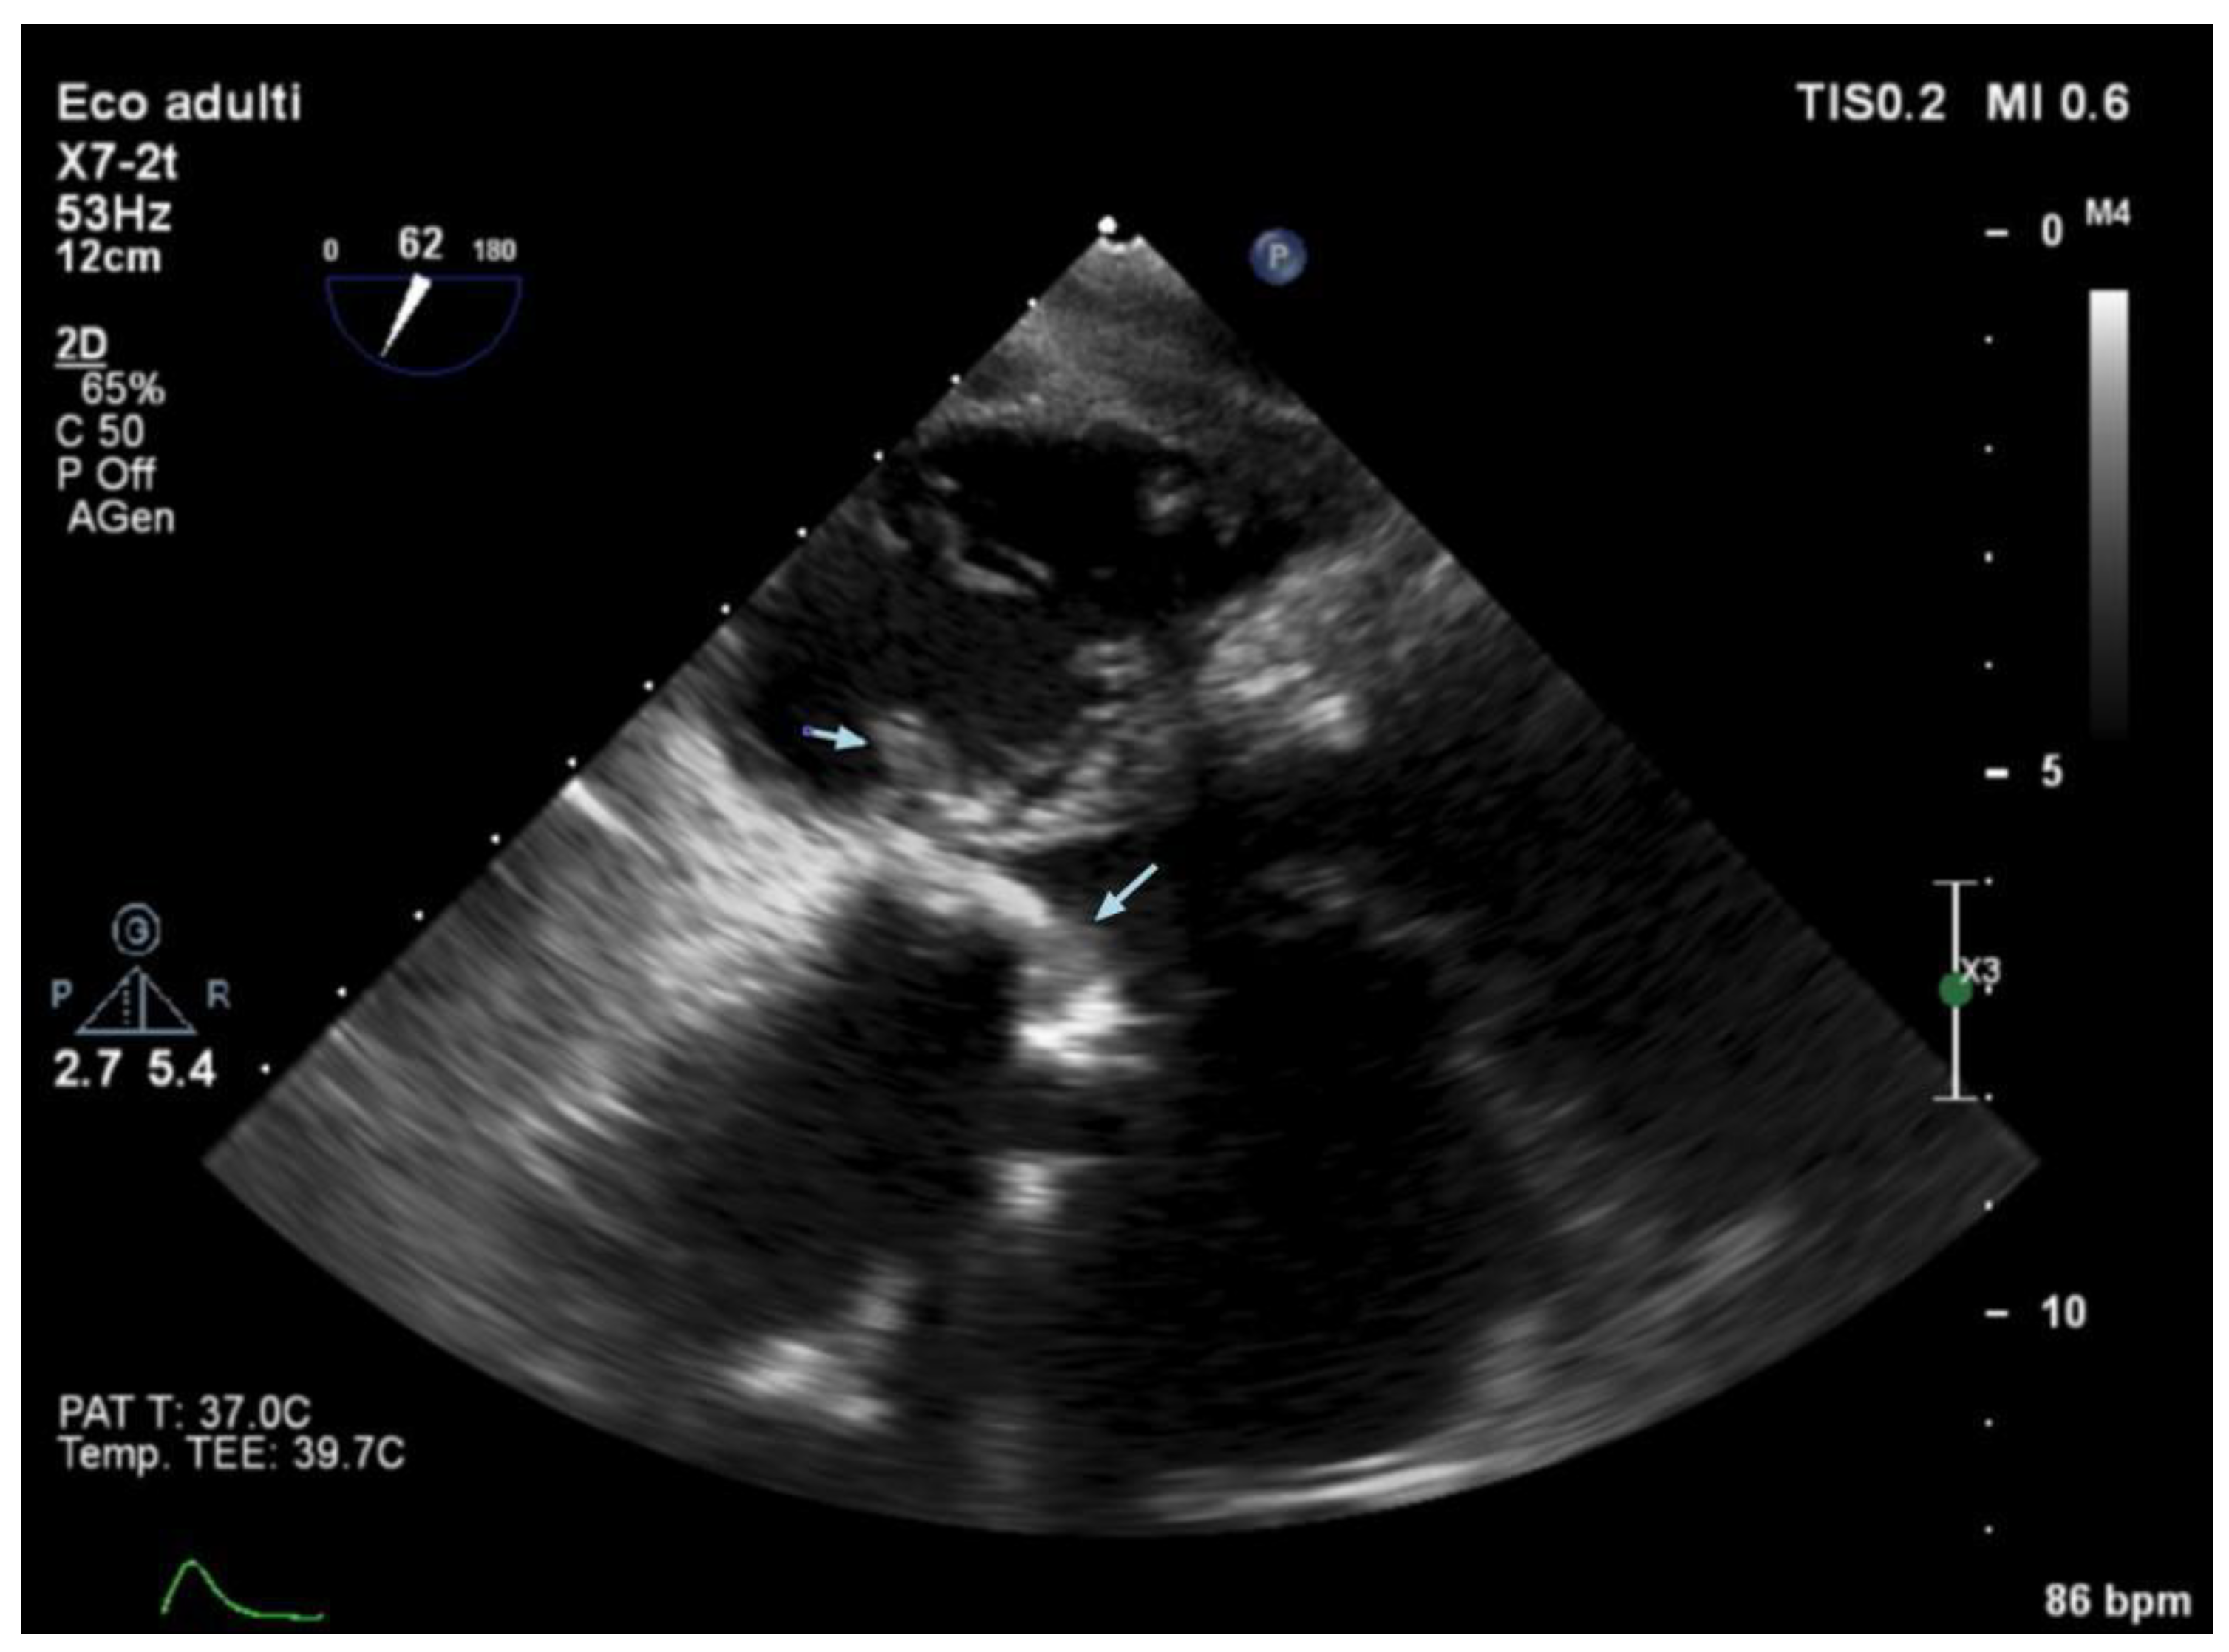

3.5. Echocardiography and Localization of IE